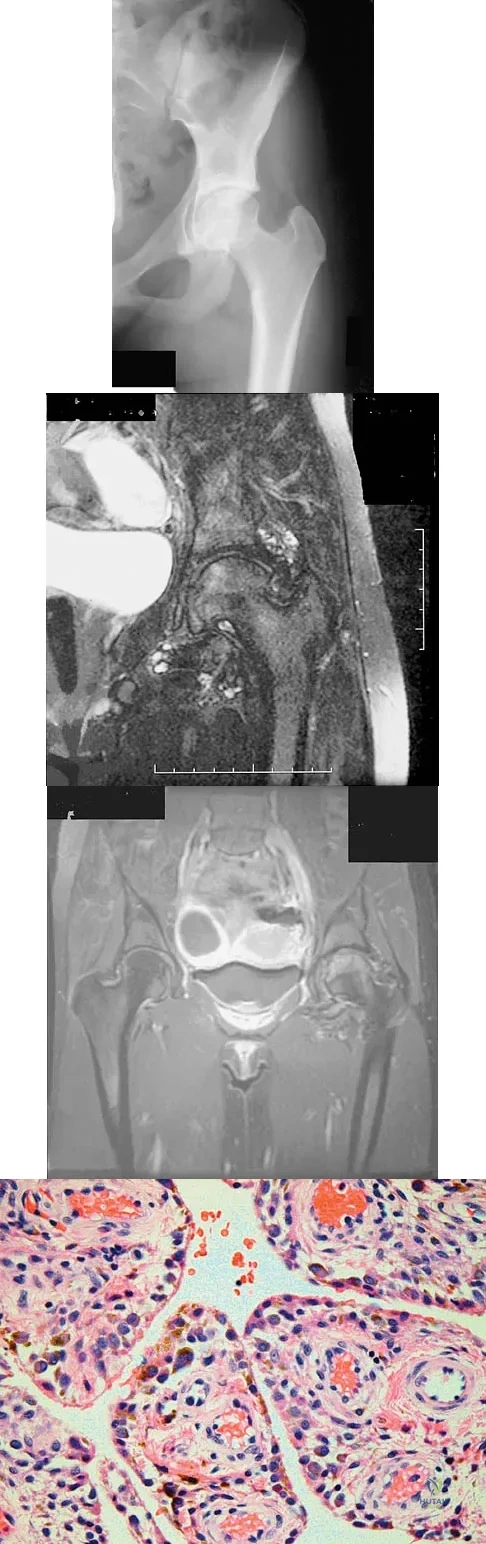

Question 90

Figures 1a through 1c show the radiograph and MRI scans of a 16-year-old patient who has a painful hip. Examination reveals a significant limp, limited abduction and internal rotation, and severe pain with internal rotation and adduction. A biopsy specimen is shown in Figure 1d. What is the deposited pigment observed in this condition?

Explanation